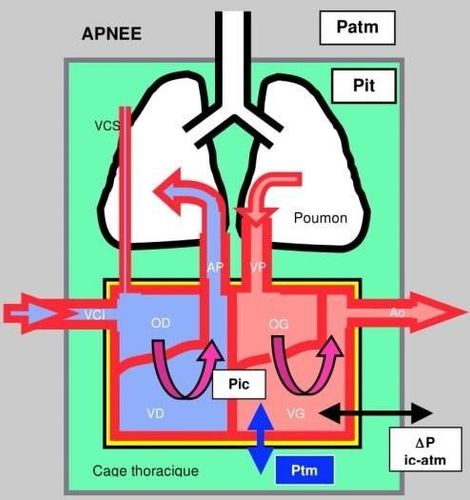

5. Đo cung lượng tim

Cung lượng tim được đo bằng phương pháp pha loãng nhiệt bằng phương trình Stewart-Hamilton. Phép đo là đáng tin cậy nếu lưu lượng phổi và thể tích máu không đổi trong các phép đo (tối thiểu 3 lần đo), nếu chỉ số (NaCl 0,9% hoặc glucose 5% ở 4-6 ° C) không trải qua bất kỳ mất mát hoặc tuần hoàn nào, không có hở van ba lá (đánh giá thấp cung lượng tim) cũng như shunt trong tim (đánh giá quá cao cung lượng tim).

Vận chuyển oxy và tỷ lệ DO2 / VO2

Để đảm bảo oxy hóa tế bào, vận chuyển (DO2) và tiêu thụ oxy (VO2) phải hài hòa. Nhu cầu trao đổi chất là yếu tố chính quyết định đến cung lượng tim, được phân phối không đồng nhất đến các cơ quan theo chức năng và nhu cầu cụ thể của chúng. Các biện pháp được thực hiện trên lâm sàng thường chỉ đánh giá mức tiêu thụ oxy nói chung.

Tất cả các hệ thống suy ra cung lượng tim từ khu vực dưới đường cong động mạch đều nhạy cảm với kháng lực mạch hệ thống và độ đàn hồi mạch máu. Chúng phải được kiểm tra lại mỗi khi thay đổi. Trong trường hợp có sự thay đổi cực độ của kháng lực mạch hệ thống (liệt mạch, co mạch mạnh) chỉ có ống thông phổi cho giá trị đáng tin cậy.